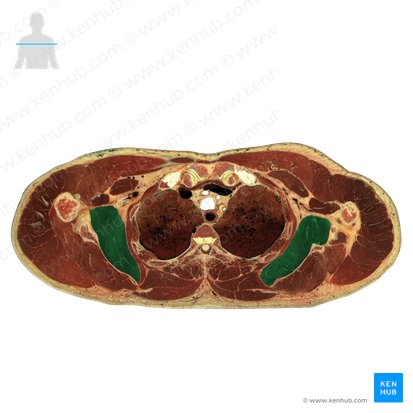

Subscapularis is a strong triangular muscle that fills the subscapular fossa of scapula. Lying posterolateral to the thoracic cage, it starts as a wide muscle whose medial two-thirds originate from the subscapular fossa of scapula and from several tendinous intramuscular septa at the ridges of the fossa. The remaining fibers arise from an aponeurosis that covers the posterior surface of the lateral third of the muscle.

The subscapularis muscle forms the majority of the posterior wall of the axilla, facing the contents of axilla with its anterior surface. Serratus anterior covers its superolateral part, while he coracobrachialis and biceps brachii muscles lie over its inferomedial part. Fascial spaces between the subscapularis, serratus anterior muscles and the thoracic cage are filled with loose connective tissue that facilitates the gliding movements of the scapulothoracic joint. The central part of the muscle is crossed by the cords of the brachial plexus and their branches, the axillary nerve, axillary artery and vein.